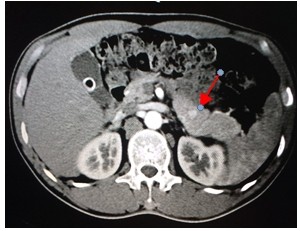

4.胰島素瘤的定位檢查

經(jīng)腹部超聲、內(nèi)鏡超聲、胰腺灌注CT、奧曲肽顯像,必要時(shí)進(jìn)行選擇性動(dòng)脈造影。